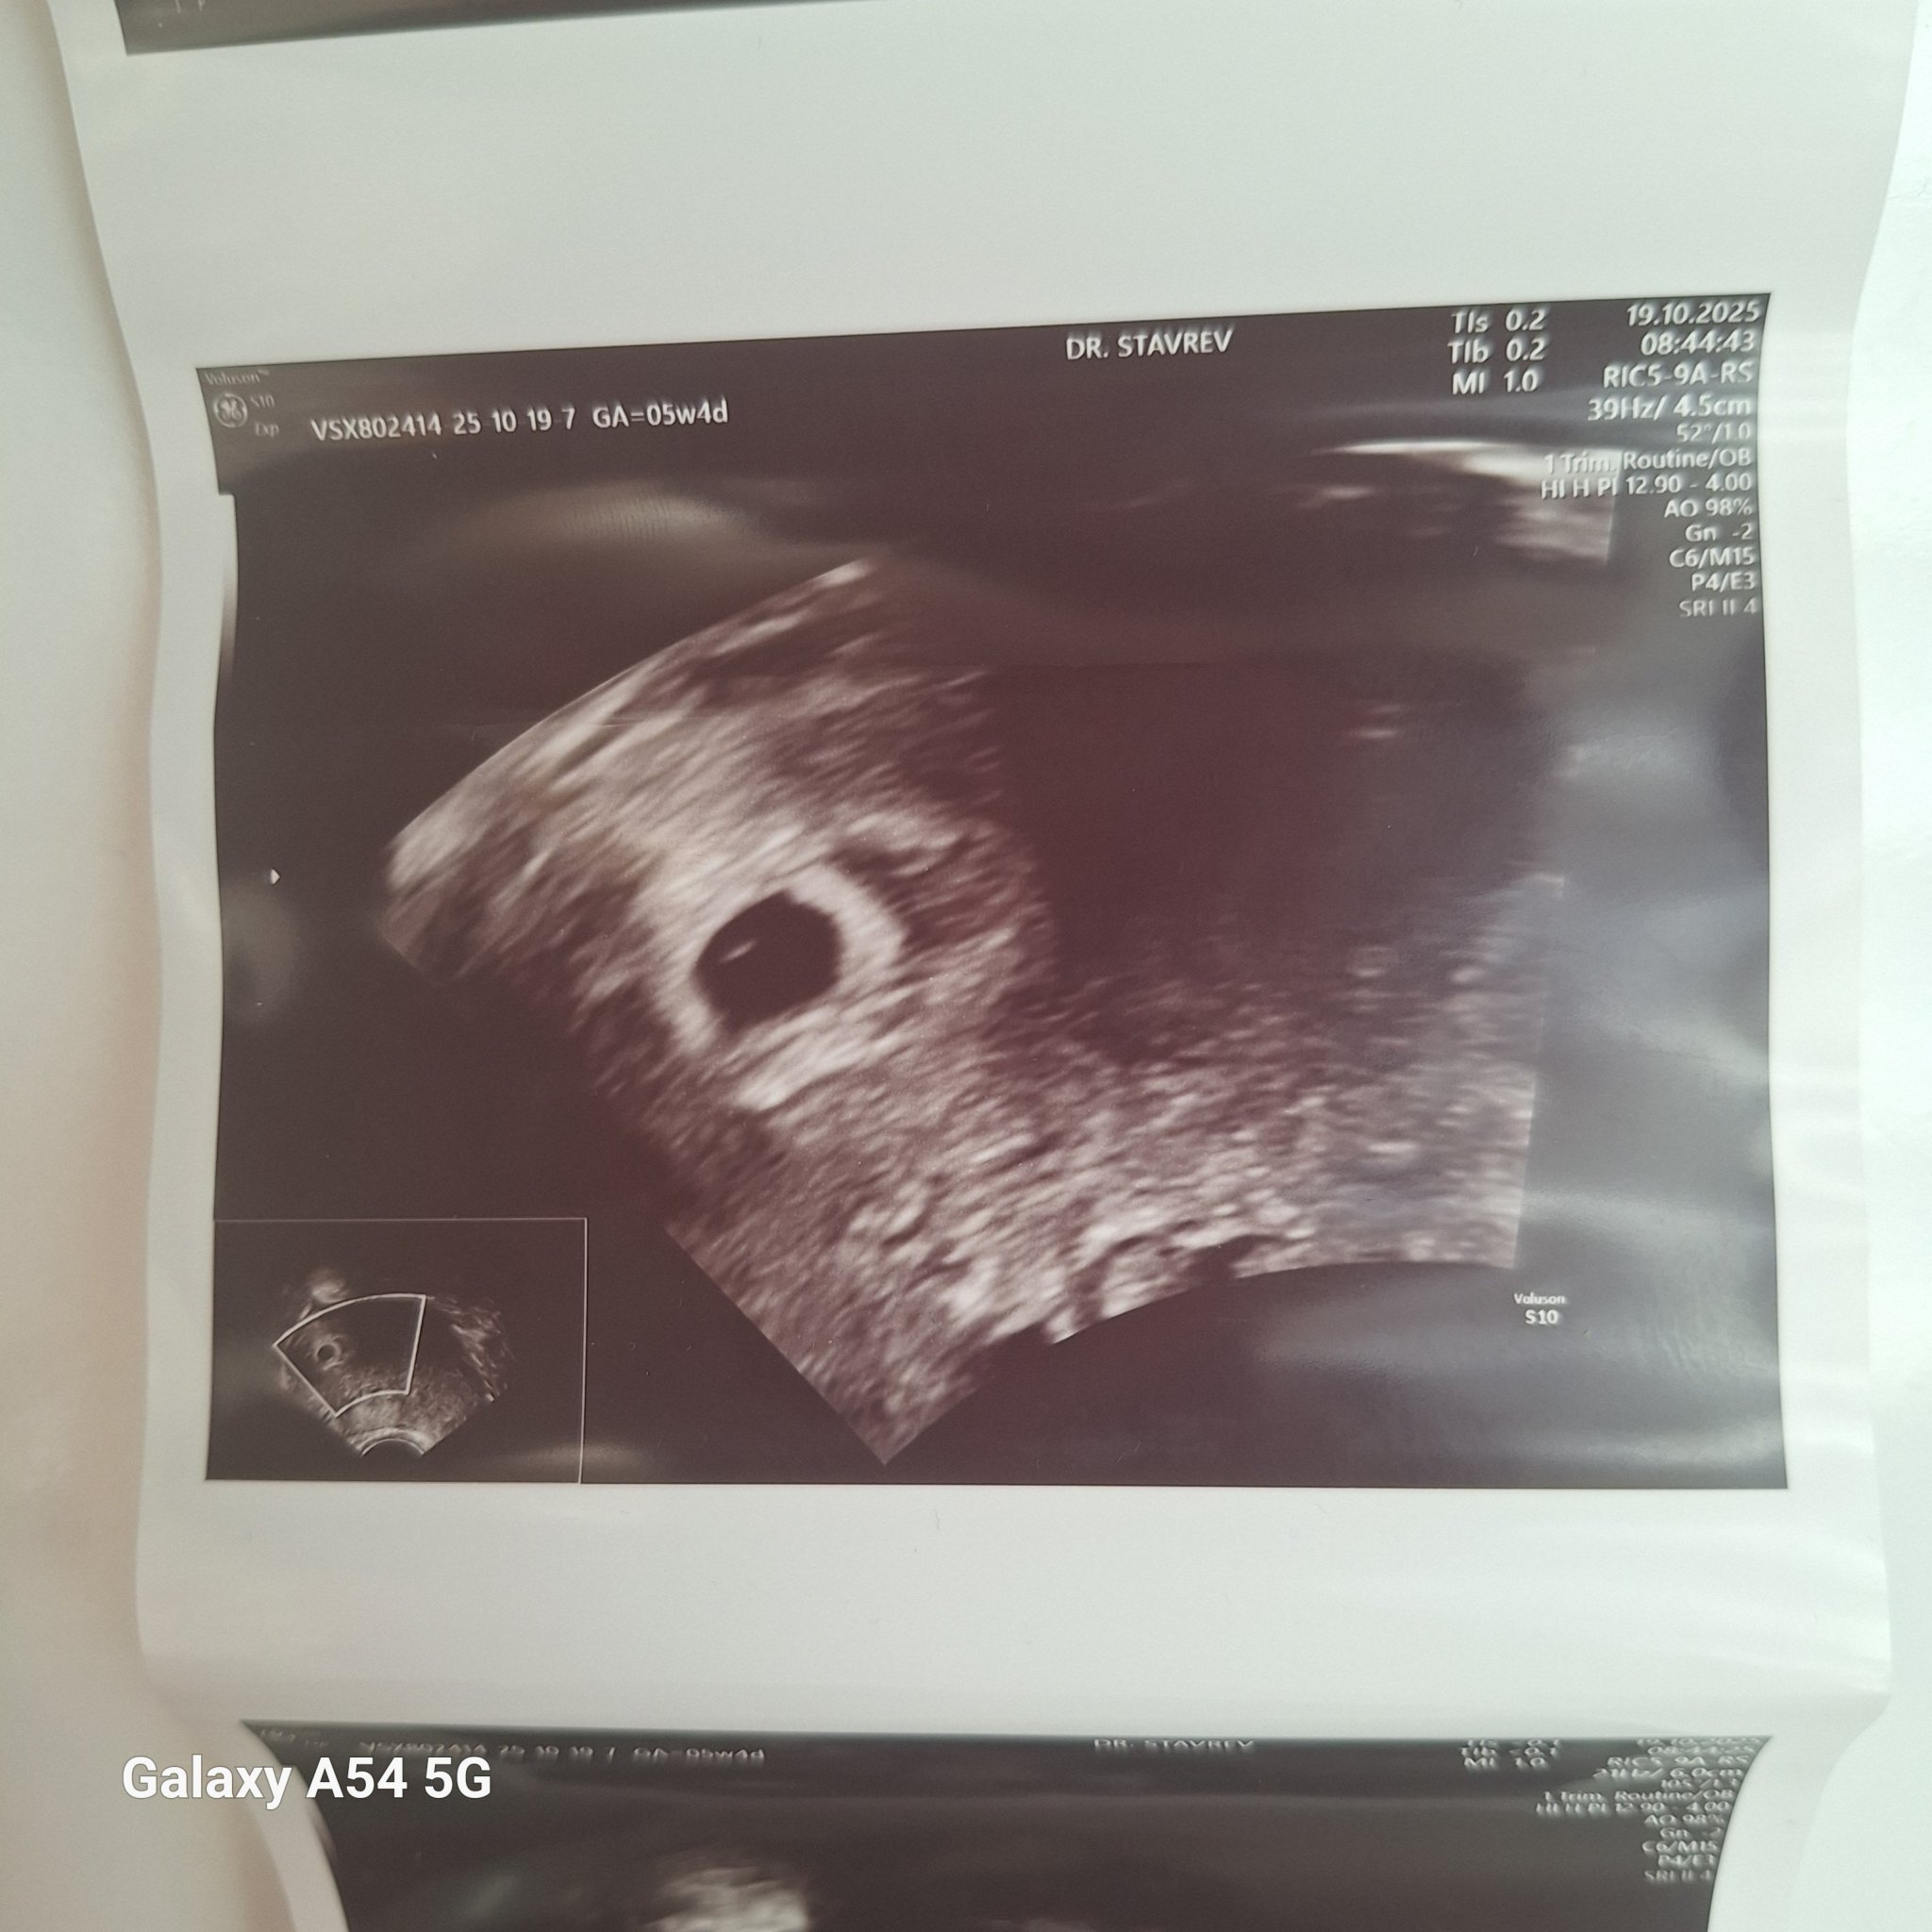

Какво представлява изображението от ехографията на 5-седмична и 2-дневна бременност?